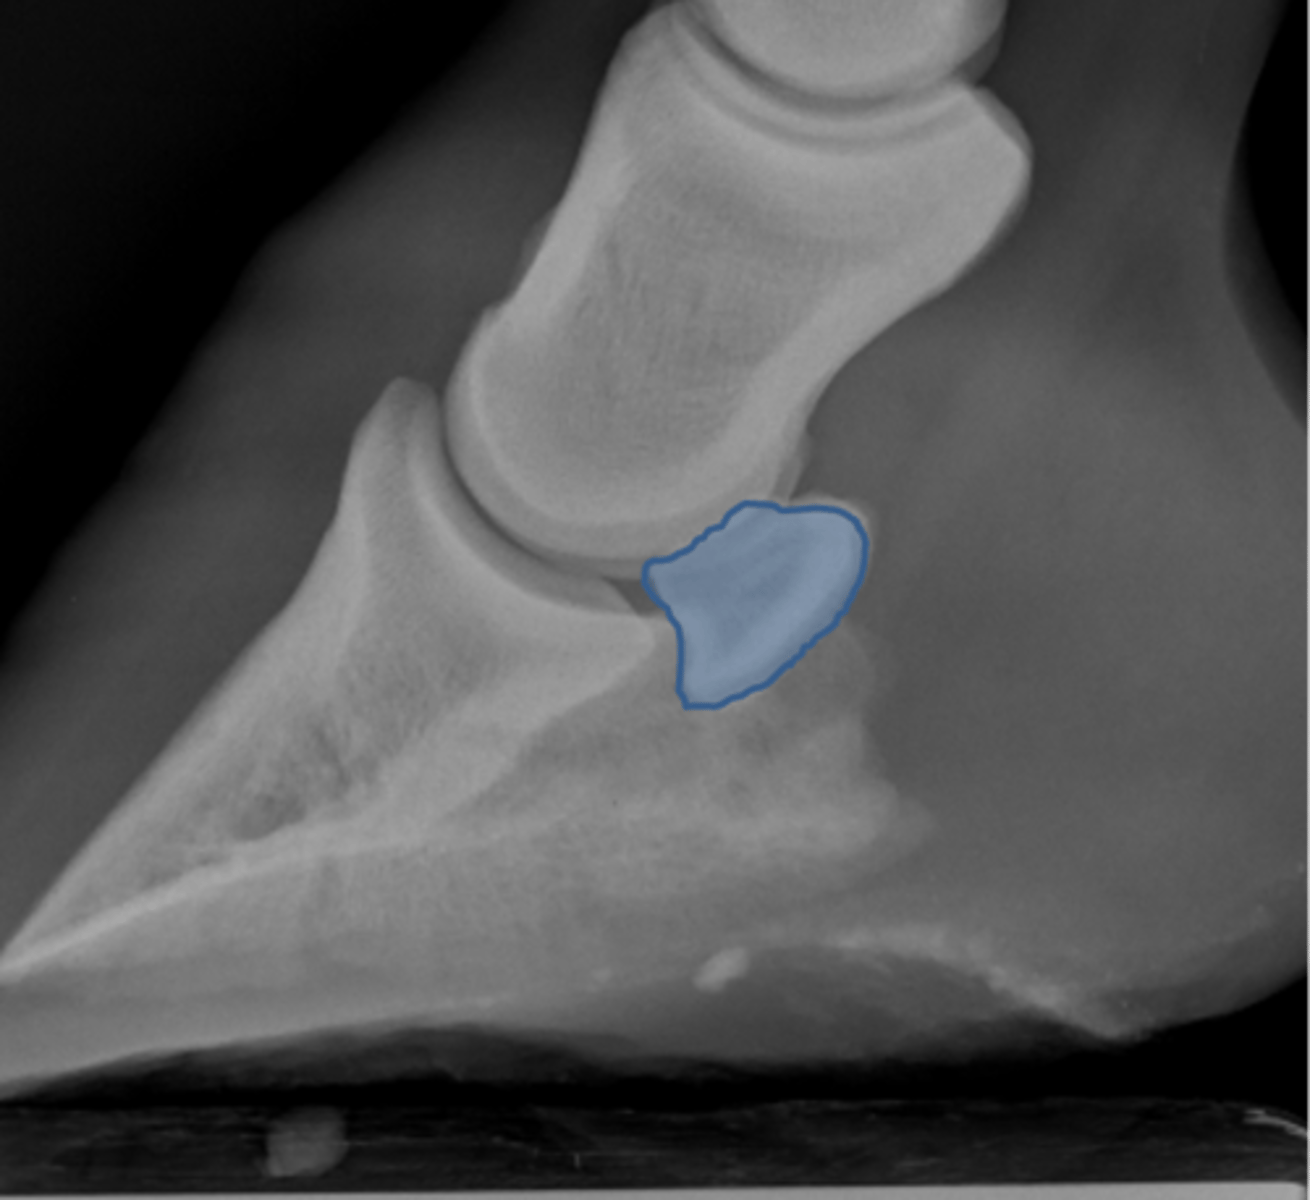

Pastern joint, LM

ID joint and view

Pastern joint, DP

ID joint and view

Short pastern (P2)

Long pastern (P1)

Pastern joint (proximal interphalangeal joint)

Distal sesamoidean ligament

What attaches at EOP?

Collateral ligament of the coffin joint

What attaches at EOP?

Long pastern (P1)

Short pastern (P2)

Medullary cavity

Ergot

Collateral ligament of the coffin joint

What attaches at EOP?

Nutrient foramen of P2

Extensor process of P3